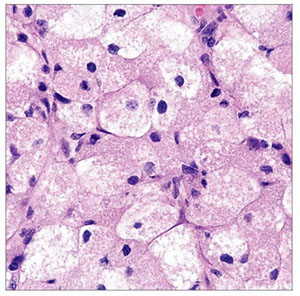

Hemangioblastoma

Adolescents and adults

- Cyst with a mural nodule in the cerebellum of an adult?

= Hemangioblastoma!

- cerebellar hemangioblastoma can secrete erythropoietin (similar to RCC)

Imaging: Cyst c enhancing mural nodule

- often cerebellar, can be cerebellar and retinal

Micro: 2 parts

- Stromal cells in neoplastic part with foamy clear cytoplasm

- delicate capillary network (non-neoplastic?)

~1/4 related to von Hippel Lindau syndrome, due to VHL gene mutation of cr 3p (3 letters in vHL)

- Must be able to distinguish from met clear cell RCC (RCC has +EMA, - inhibin; hemangioblastoma is the opposite)

IHC: (+) nested reticulin positivity, inhibin, Oil red O, Aquaporin-1, NSE

- neg: EMA, CKs, PAX2/8, CAIX, RCC< CD10

DDx: Renal cell carcinoma (should stain negative with RCC markers)

- similar to RCC, hemangioblastoma can secrete erythropoietin